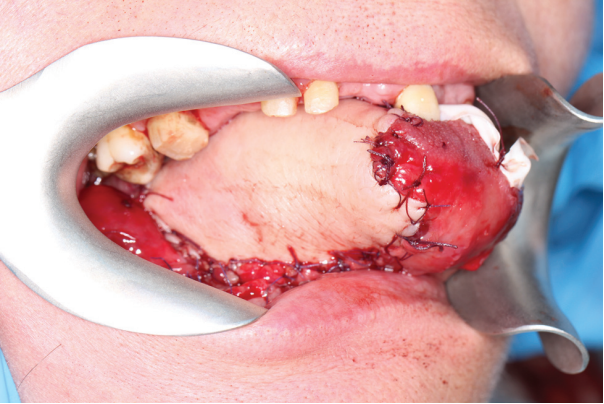

After affixing the skin site of the flap to the remaining part of the tongue with guiding sutures, the donor vessels were carried out in a tunnel formed in the soft tissues of the floor of the mouth, after which the microsurgical stage was performed. Anastomosing of the radial artery with the facial artery was performed in all cases according to the type of “end-to-end” anastomosis; similarly, vena comitans were anastomosed with the external jugular vein. At the final stage, neurorrhaphy of the lateral cutaneous nerve and lingual nerve was performed in two cases, while neurorrhaphy of the hyoid nerve (end-to-side type) was also carried out in two cases. The average time of the microsurgical stage was 45 min. After restarting the blood flow, the filling of the donor vessels was assessed visually and using a portable Doppler Minidop (Bioss). When the flap had been successfully adapted to the remaining part of the tongue with resorbable Vicryl 3.0 thread, layer-by-layer wound closure was performed (Fig. 5).

The postoperative period in most patients was uneventful. Only one patient had venous stasis of the flap 3 hours after the surgical intervention; in this case, a revision surgery with repeated venous anastomoses was performed. The postoperative period passed further in this patient without peculiarities. The nasogastric tube was removed in all patients on the 12th day; the average period of hospitalization was 14 days (Fig. 6).

Fig. 5. View of the flap after suturing the wound and restarting the blood flow